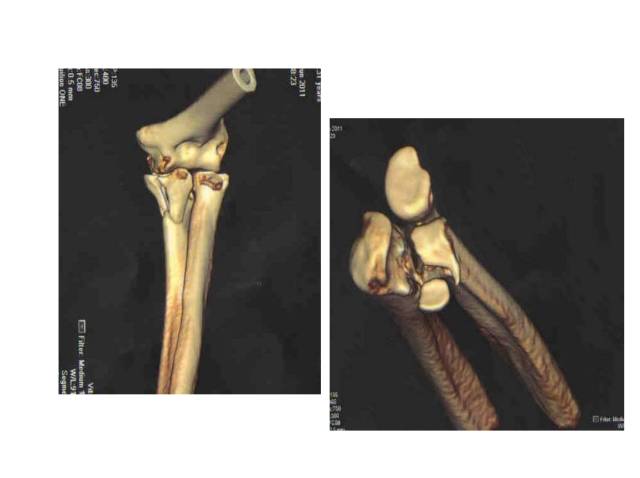

尺骨近端

• 鹰咀:180 °半月切迹,与骨干成30 °角,肱三头肌止点

• 冠突:最重要骨性稳定结构

• 尺骨粗隆:肱肌止点

• 桡切迹:70 °,冠突下方

• 骨干:1-6 °外翻,参与提携角

• 后方:旋后肌嵴

冠突是一个非常重要的稳定结构

• Ⅰ型和Ⅱ型单纯冠状突骨折,发生后方半脱位的风险很小,允许早期活动

• 即使单纯Ⅲ型骨折,在很小的生理应力下也有可能发生后方半脱位,特别是在屈肘60°~105°,支持对Ⅲ型损伤ORIF